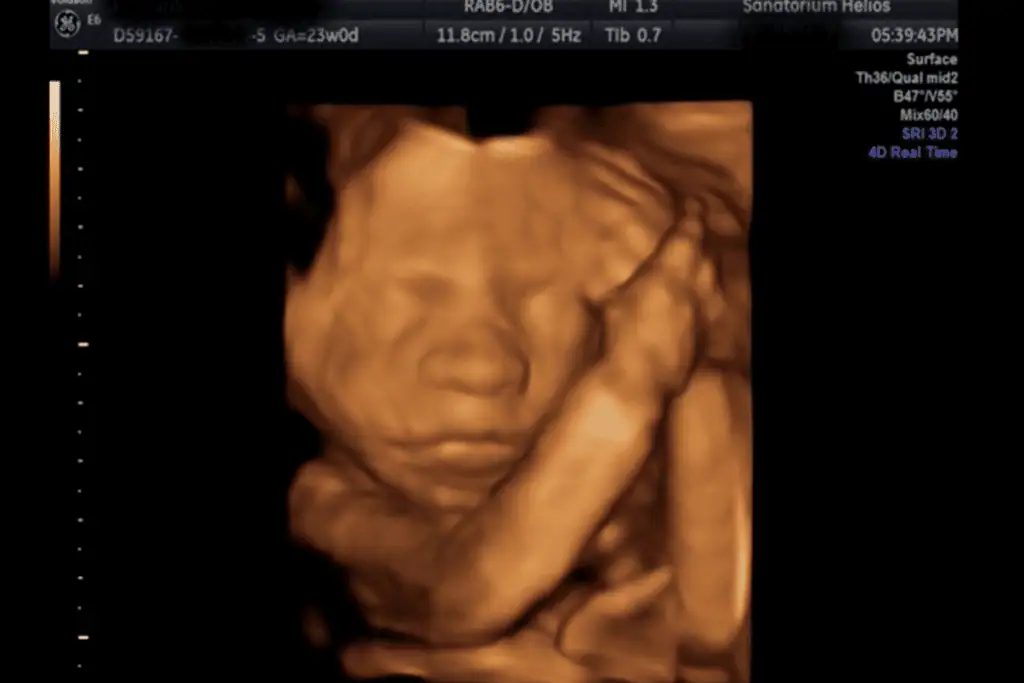

3D, 4D Ultrazvuk

Jako třetí pracoviště v České republice a jako první privátní zařízení mělo Sanatorium Helios k dispozici trojrozměrný ultrazvuk GE Voluson 730. Nově je možné také vyšetření na nejmodernějším přístroji Voluson E10.

Nejvhodnější je záznam plodu mezi 20. – 26. týdnem těhotenství.

Kvalita záznamu na 3D/4D je vždy ovlivněna polohou plodu a polohou placenty, množstvím plodové vody a konstitucí pacientky. Pokud je např. plod přitisknut k děložní stěně nebo k placentě ev. má před obličejem ruce nebo nohy, je zobrazení na 3D velmi nepřesné a mnohdy nejdou kontury tváře vůbec zobrazit.

Ze 3D a 4D ultrazvukového vyšetření lze pořídit fotografii či DVD záznam.

Tyto fotografie jsou pořízené přístrojem Voluson 730